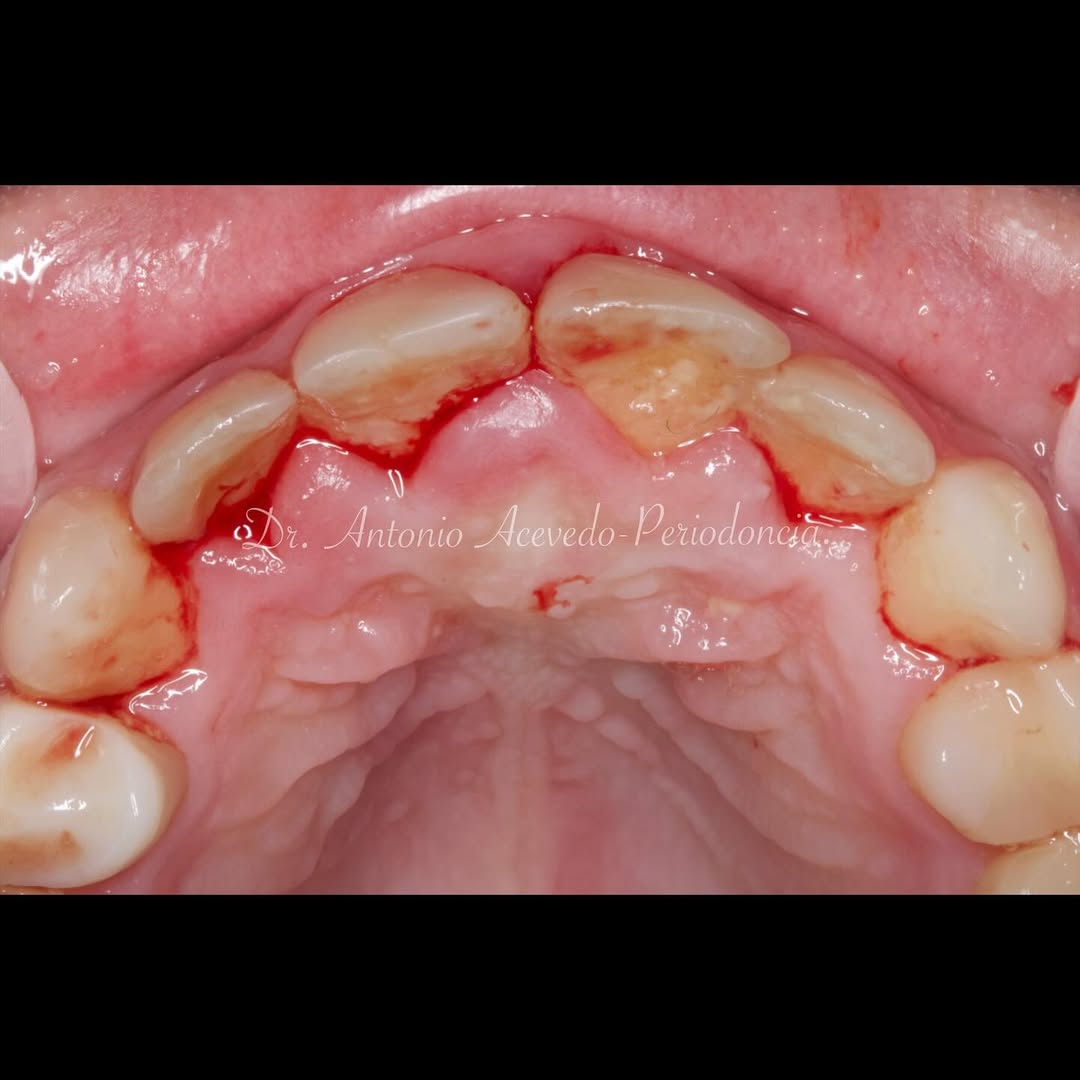

Durante una mañana, asistirás a una Cirugía Mucogingival de recubrimiento radicular de recesiones múltiples en IV y V sextante (36 a 43).

Gracias al uso del microscopio y a la proyección en tiempo real en pantalla, verás exactamente lo mismo que veo yo durante la cirugía, sin tener que estar